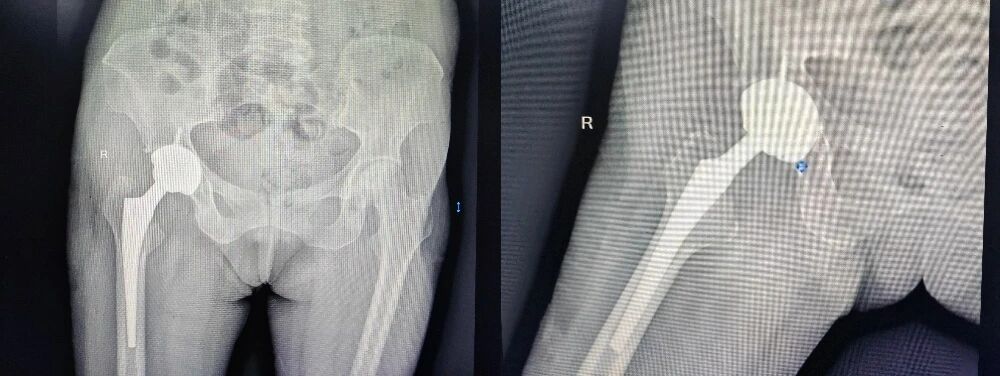

近年来,她的右侧髋关节疼痛日益加剧,从行走困难发展到夜间静息痛,甚至连简单的翻身都成了折磨。影像检查显示,她的右侧股骨头已严重塌陷、变形,关节间隙几乎消失。

骨伤科创伤关节团队则利用先进的计算机三维重建技术,在术前精准还原了严重变形股骨头的复杂形态,为假体型号选择、安放角度和骨缺损修复做好了数字化预演。

手术日,真正的挑战呈现在主刀团队眼前。当打开髋关节后,情况比影像所见更为复杂:长期激素影响下,骨骼质量极差,如同「朽木」;坏死的股骨头严重塌陷、变形,与髋臼粘连致密,正常的解剖结构已面目全非。

首先精细松解,要小心剥离粘连组织,保护重要的神经血管。接下来精准截骨,在变形的股骨颈上找到最佳截骨平面。最后重塑「地基」,患者髋臼侧存在巨大骨缺损,团队采用自体股骨头骨块进行结构性植骨,重建了髋臼的正常形态和包容性,为人工髋臼杯的稳定放置创造了条件。